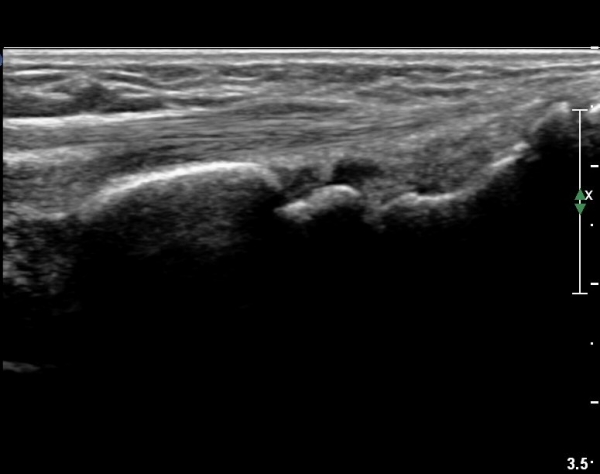

¿ä°ñ ¸»´Ü lister's tubercle ºÎÀ§¿¡¼­ Àå, ´Ü¿äÃø¼ö±Ù½ÅÀü°Ç Ⱦ´Ü¸é°Ë»ç¿¡¼­ ƯÀÌ ¼Ò°ßÀ» º¸ÀÌÁö

¾Ê´Â´Ù(»çÁø 3).